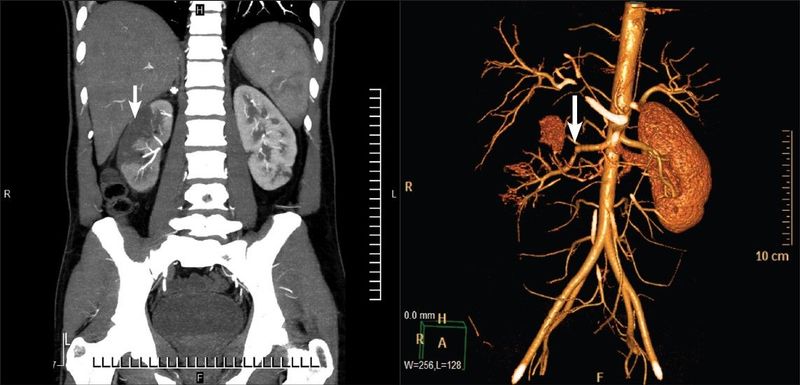

17. An 85-year-old white male presented to our Emergency Department complaining of a 1-day history of right upper quadrant and right flank pain. He stated that the pain started suddenly and seemed to originate deep within his right upper quadrant. It extended laterally into his flank. He graded the pain as “severe” and described it as sharp and constant .

On physical examination, he had a temperature of 35.5°C. Blood pressure was 126/88 mmHg, with a heart rate of 86 beats per minute. Respiratory rate was 22 per minute, with an oxygen saturation of 92% on room air.

You order a CT abdomen/pelvis with IV contrast shown below:

What underlying medical condition is likely in this patient?